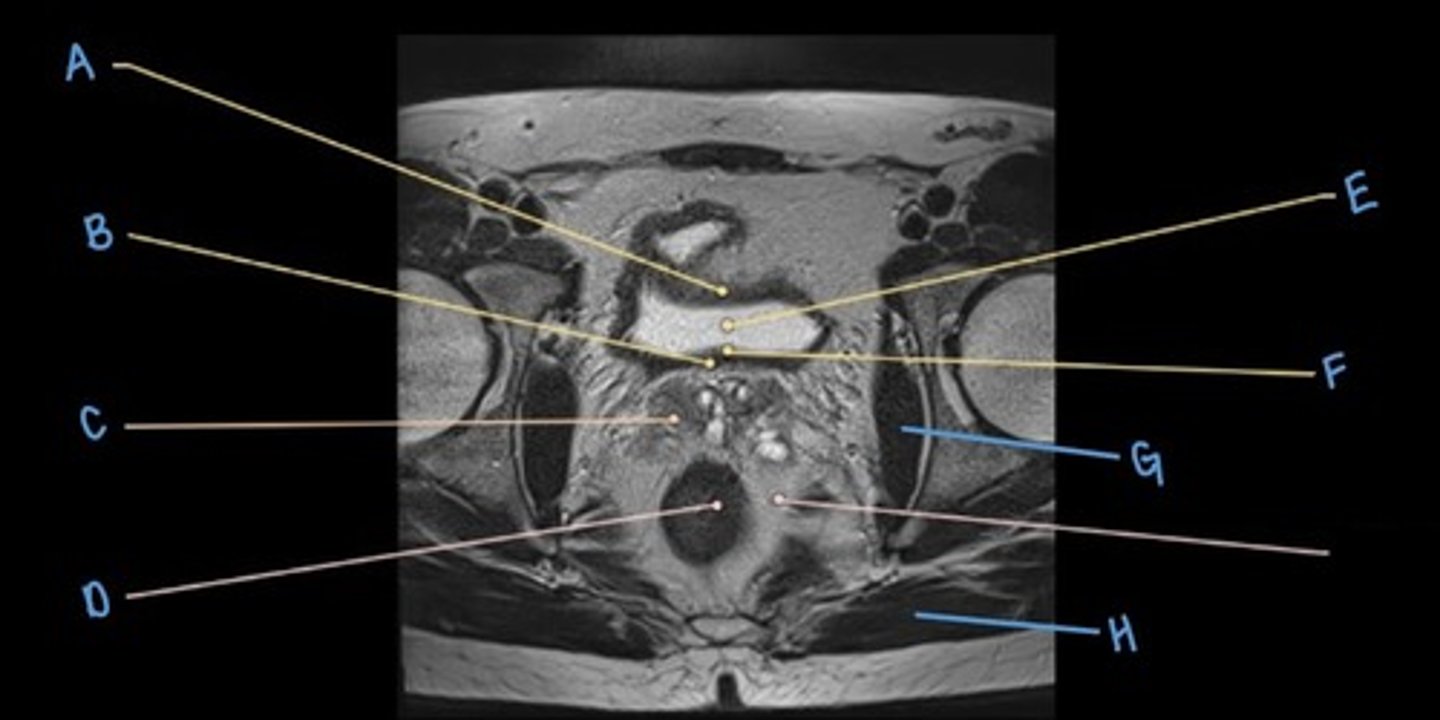

seminal vesicles

C

rectum

D

bladder

E

trigone of the bladder

F

obturator internus muscle

G

gluteus maximus muscle

H